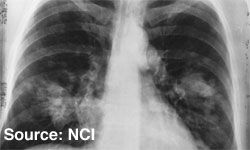

Lung cancer remains the single largest cause of cancer-related deaths, and the burden of the disease in the elderly population will only grow as life expectancy increases.

Lung cancer continues to be the leading cause of cancer-related mortality, resulting in ~1.4 million annual deaths worldwide and 160,000 deaths each year in the United States.